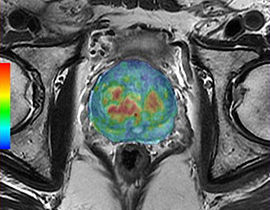

Mit der MRT können sowohl anatomische als auch physiologische Merkmale von Organen und Pathologien erkannt werden. Diese Vielseitigkeit macht die Bildgebungsmethode zu einem unverzichtbaren Diagnosewerkzeug. AW-Programme mit ihren vereinfachten Abläufen und intuitiver Benutzeroberfläche ermöglichen dem Anwender eine rasche und präzise Quantifizierung und qualitative Auswertung von MR-Untersuchungsergebnissen.

Erweiterte Visualisierung für MR